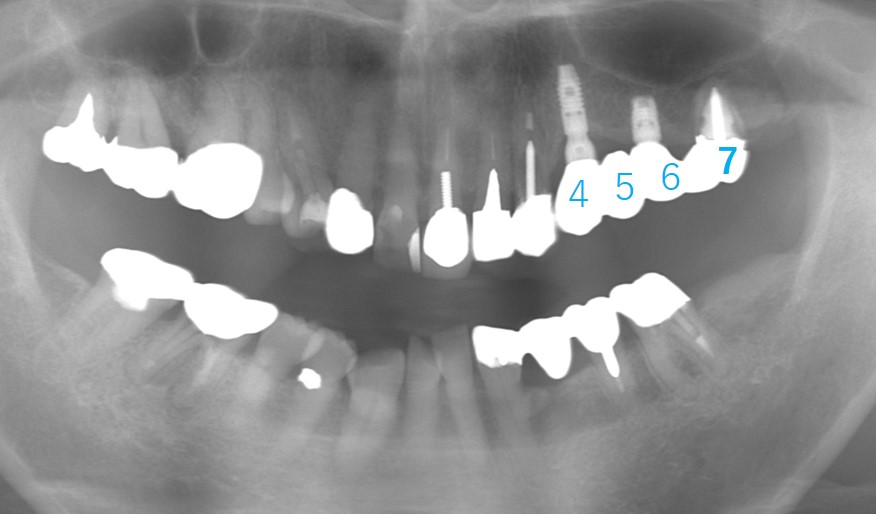

移植後2年経過しました。

移植した歯の周囲には歯槽骨の再生も確認でき、良好に経過しています。